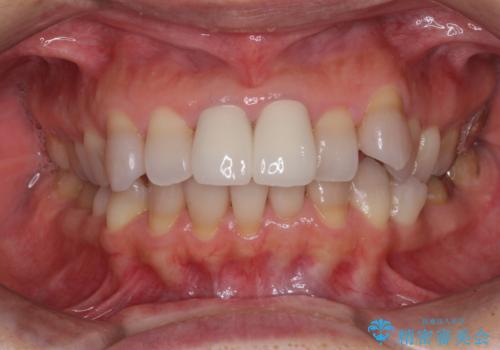

- 変色した前歯2本を気にして来院された患者様です。

右側の前歯は根管治療を行い、その後2本とも歯質に近い素材の土台を植立してオールセラミッククラウンにて補綴することとしました。

神経を取り除いた歯は、経年劣化により変色してしまいます。

前歯は審美的に、奥歯は強度的に問題が起きるため、早めにクラウンを装着することが望ましいとされています。